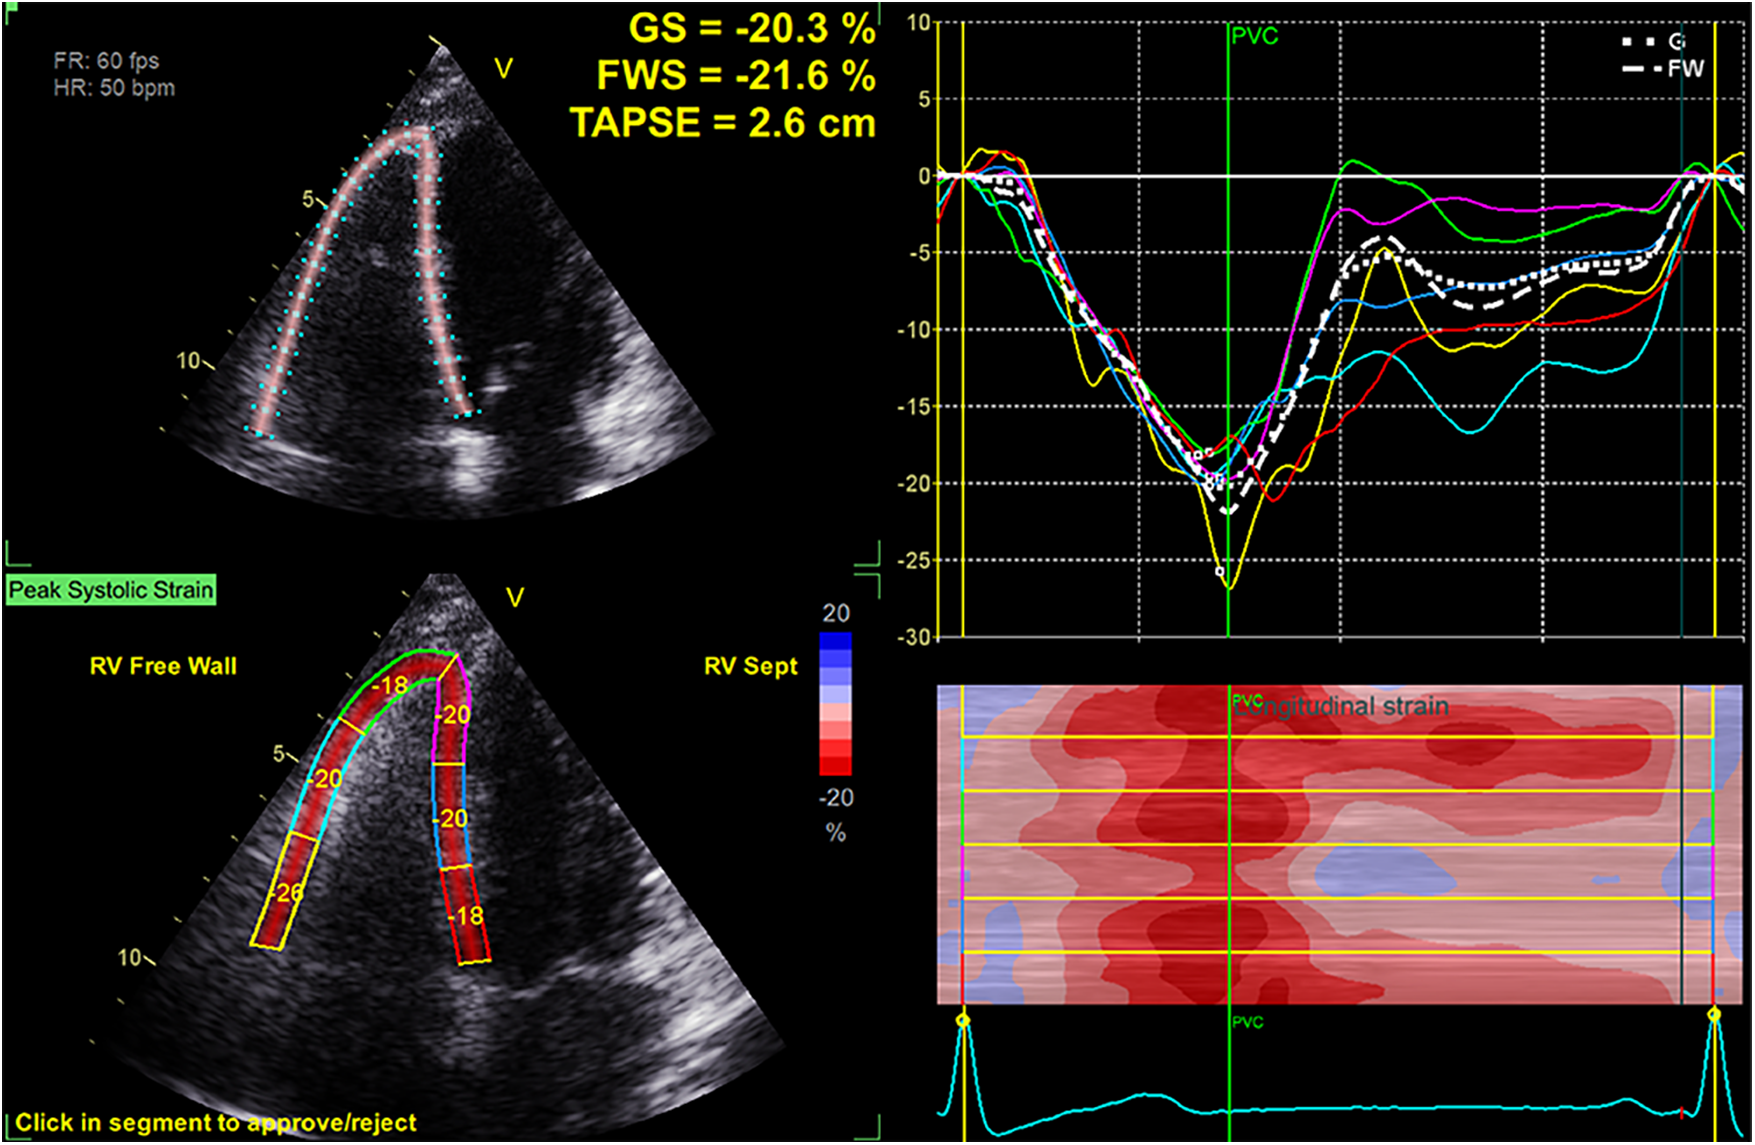

Dynamic images capturing a minimum of three consecutive cardiac cycles were saved (in DICOM format) in the RV-focused apical 4-chamber view. Strain analysis was conducted using the EchoPac workstation (GE, version 204, Horten Norway). A region of interest was established following the selection of the tricuspid annulus and apical plane, and the tracing curve was manually fine-tuned to achieve optimal alignment. The software algorithm automatically computed the RV-GS, RV-FWS, and strain values for each myocardial segment (Figure 1). To minimize information bias, data collection was performed by two experienced sonographers who were blinded to the clinical data.

Figure 1

Measurement of RV-FWS and RV-GS in an RV-focused apical four-chamber view.